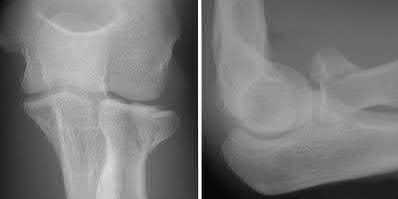

A 25-year-old woman sustains a fall on an outstretched hand. She complains of elbow pain. Examination reveals tenderness over the lateral elbow and pain on elbow motion. Injury radiographs and CT scans are shown in Figures A and B, respectively. What is the next best step?

This patient has Mason II radial head fracture. ORIF will give the best results.

Non-/minimally displaced radial head fractures without a block to rotation can be managed nonoperatively. Complete articular fractures with >=3 fragments do better with radial head replacement. Indications for ORIF include large articular surface fragments, > 2 mm of displacement, mechanical block to forearm rotation, or associated fractures or ligament injuries requiring surgery.

Figures A and B are radiographs and 3D reformatted CT images showing a displaced partial articular radial head fracture.